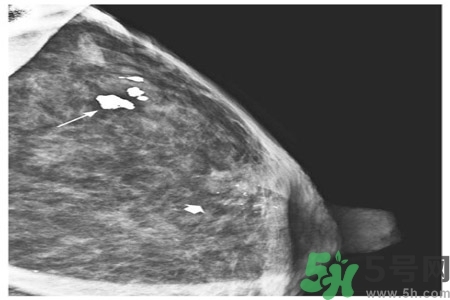

成簇樣微小鈣化常是早期乳腺癌唯一的X線征象。根據(jù)微小鈣化形態(tài)、大小、數(shù)量和密集度等表現(xiàn)可反映病變性質(zhì)和范圍。微小鈣化點(diǎn)可位于腫塊內(nèi)或周圍,總數(shù)目6~15枚,密度不均,大小不等。

乳腺X線檢查可提高隱匿癌、微小癌(直徑小于10mm)和早期癌的診斷率。直徑小于10mm腫塊定性困難,但細(xì)沙型鈣化常是惡性病變的警報(bào);若同時(shí)出現(xiàn)周圍結(jié)構(gòu)紊亂,雙側(cè)不對(duì)稱,血管影增粗等征象則惡性病變可能性更大。